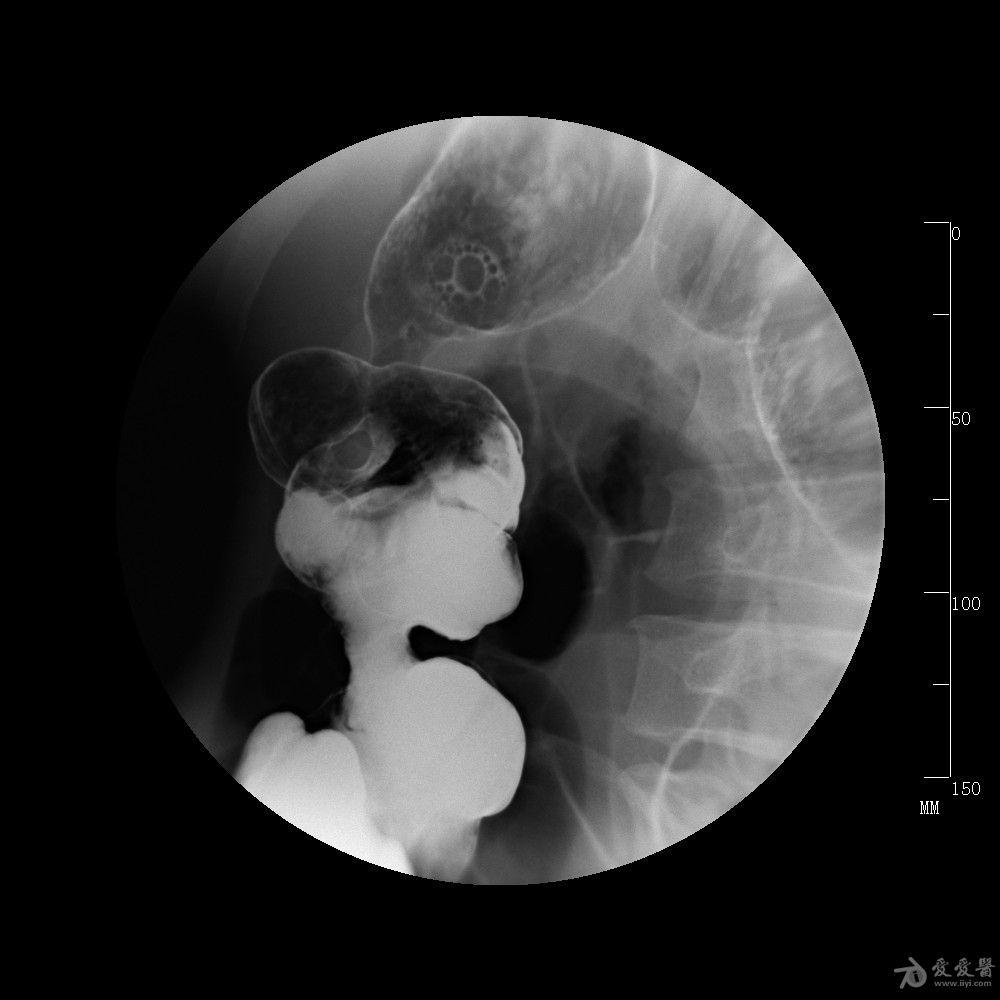

哎呀,说到克罗恩病在肠镜下的表现,那真是一场让人心疼的景象。想象一下,那些平时默默工作的肠道,突然间变得像是经历了战火的废墟。肠壁上,那些原本光滑柔软的地方,现在却布满了溃疡,就像是大地被无情地撕裂开来。

这些溃疡,有的深,有的浅,有的还在不停地渗出液体,就像是伤口在不停地哭泣。更让人揪心的是,这些伤口之间,还夹杂着一些狭窄的区域,肠道在这些地方被挤压得几乎要窒息。这不禁让人想到,肠道在无声地呼救,希望能有人听到它的痛苦。